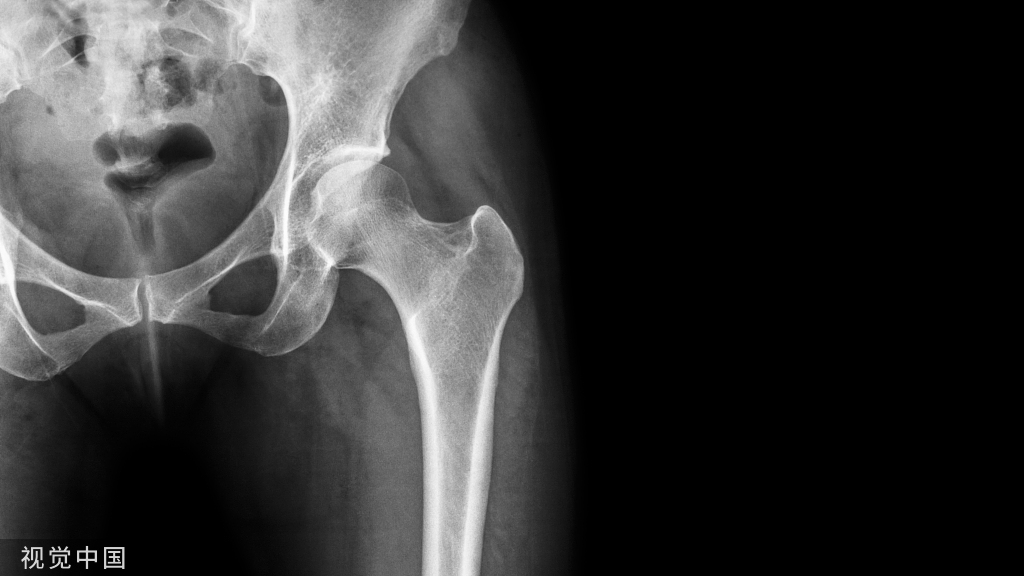

假体周围骨折特点

常规固定方法难以应用

骨折部位常合并有不同程度骨丢失与骨缺损

必须考虑到假体的稳定性

骨质疏松

各种原因导致的骨质疏松

·年龄

·原发疾病造成的骨质疏松

·医源性因素造成的骨质疏松

(长期服用类固醇类药物/既往多次手术/骨溶解)

·废用性骨质疏松

➤骨溶解

局部或广泛的骨溶解

导致骨量丢失、骨皮质变薄

骨折(尤其是在假体柄尖端的骨溶解)